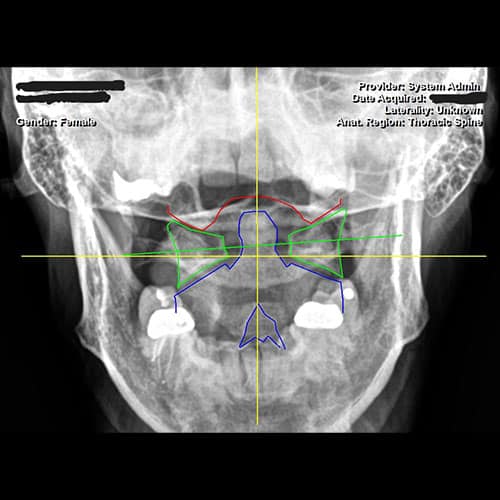

x-ray of atlas subluxation